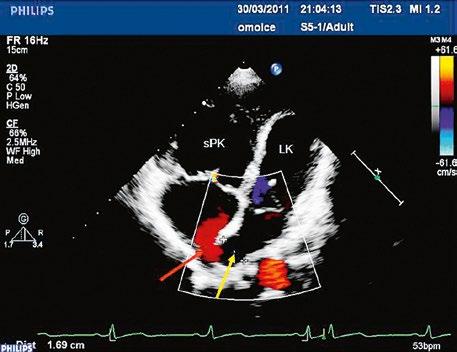

Obr. 45.14 TTE, čtyřdutinová apikální projekce. Kompletní atrioventrikulární septální defekt je označen křížky, představuje komunikaci mezi oběma síněmi i komorami se společnou atrioventrikulární chlopní (AVch)

LK – levá komora, LS – levá síň, PK – pravá komora, PS – pravá síň